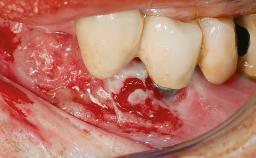

Removal of a Malpositioned Implant and Direct New Implant Placement with Simultaneous Contour Augmentation using GBR

A 35-year old female patient was referred to the Department of Oral Surgery and Stomatology at the University of Bern, Switzerland, for examination of an implant site that had exhibited clinical signs of slightly delayed wound healing. In addition, the referring clinician found no evidence for a facial bone wall when she raised a flap to gain access to the implant for abutment connection. Four months earlier, she had inserted a bone-level implant in a single-tooth gap, where the lateral incisor had been extracted due to a chronic periapical lesion on the mesial aspect of the root. Implant placement was combined with simultaneous bone augmentation using deproteinized bovine bone mineral (DBBM, Bio-Oss®; Geistlich, Wolhusen, Switzerland) and a collagen membrane (Bio- Gide®; Geistlich), followed by primary wound closure. The patient also provided the postsurgical radiograph that displayed the implant with a 3.5-mm healing cap.